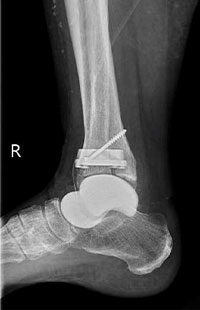

足くびの外側から手術を行う外側侵入型の人工足関節です。

この手術では、まず腓骨を骨切りし、足くびの外側からアプローチします。そこから脛骨と距骨で構成される「距腿関節(きょたいかんせつ)」の表面を削り、人工関節を設置します。特に、距腿関節のみが変形しており、距骨自体のつぶれや他の関節の障害がない方に向いています。人工関節は金属と医療用の特殊な素材でできています。

術前

術後